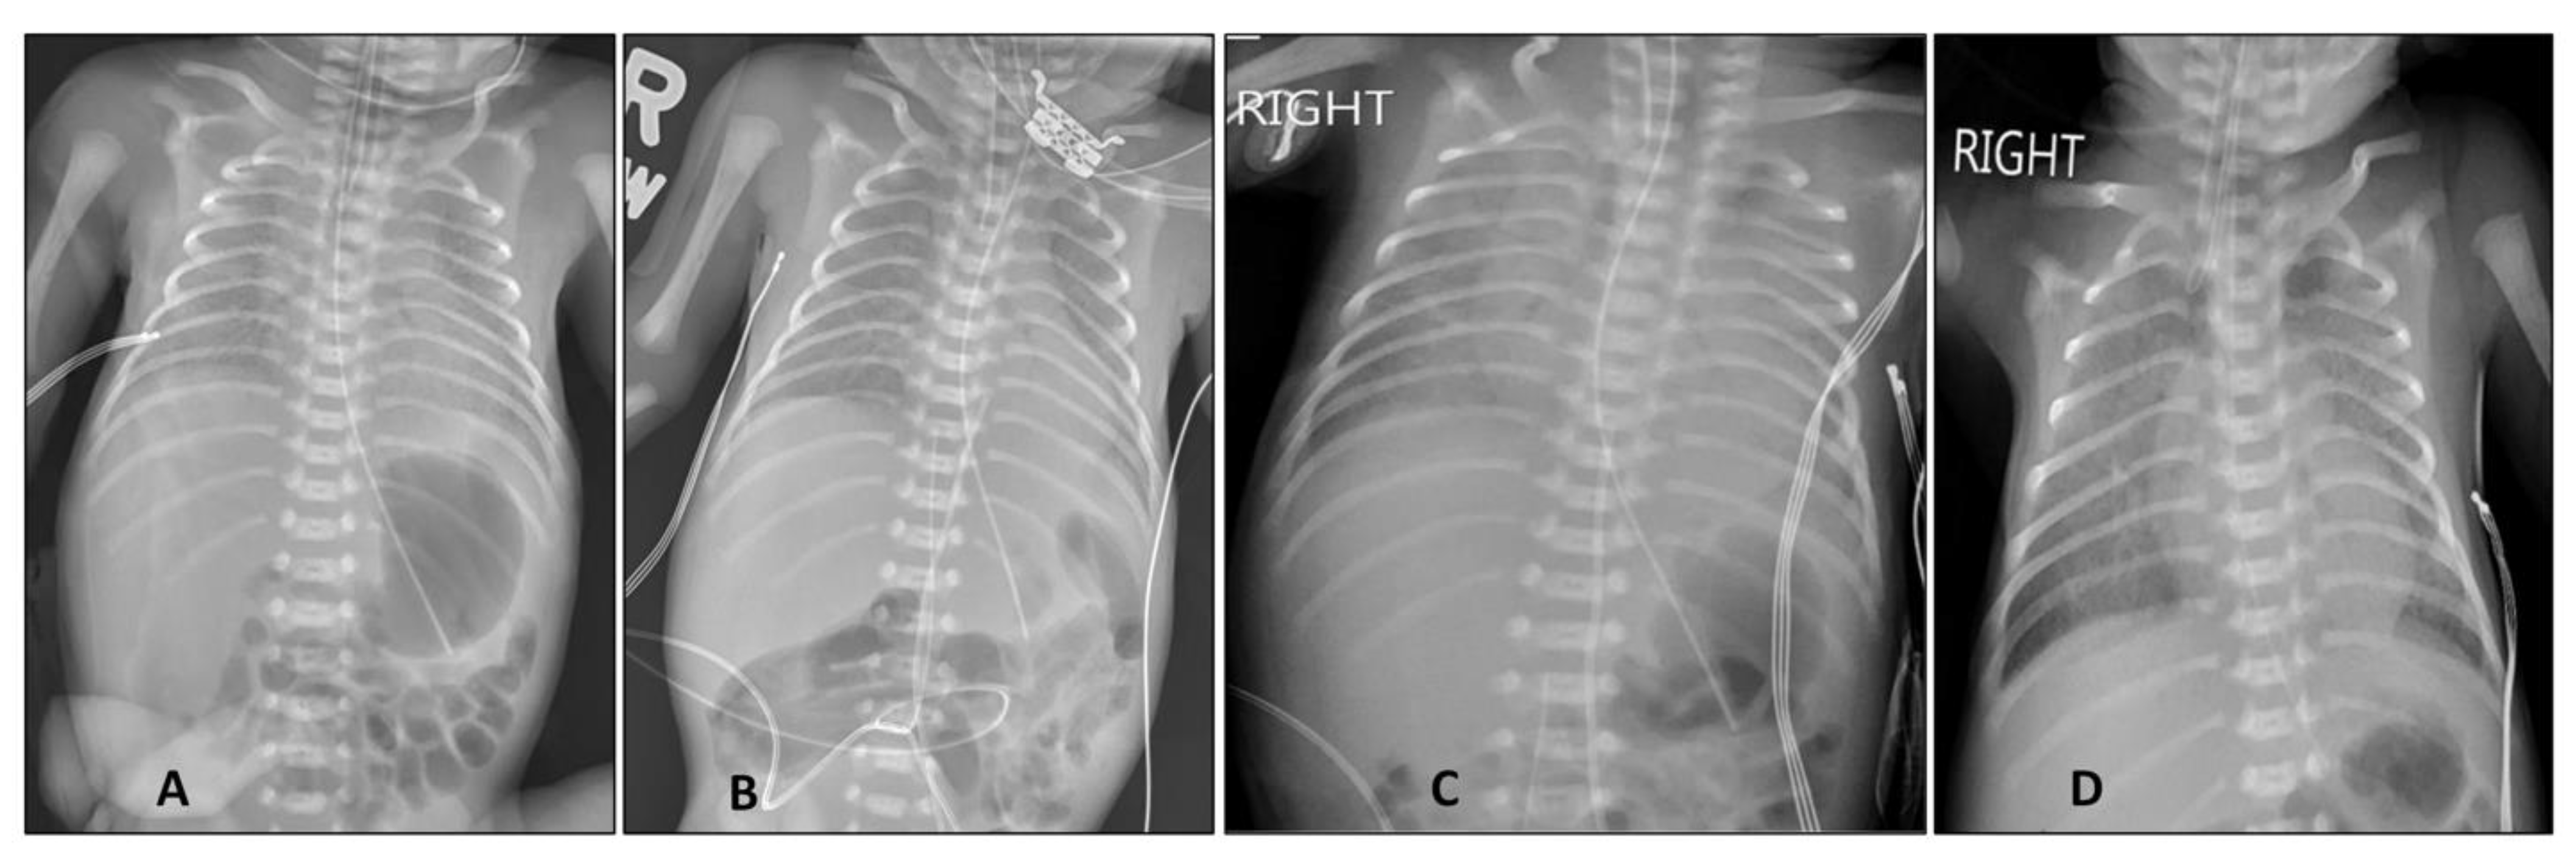

2. Case Report